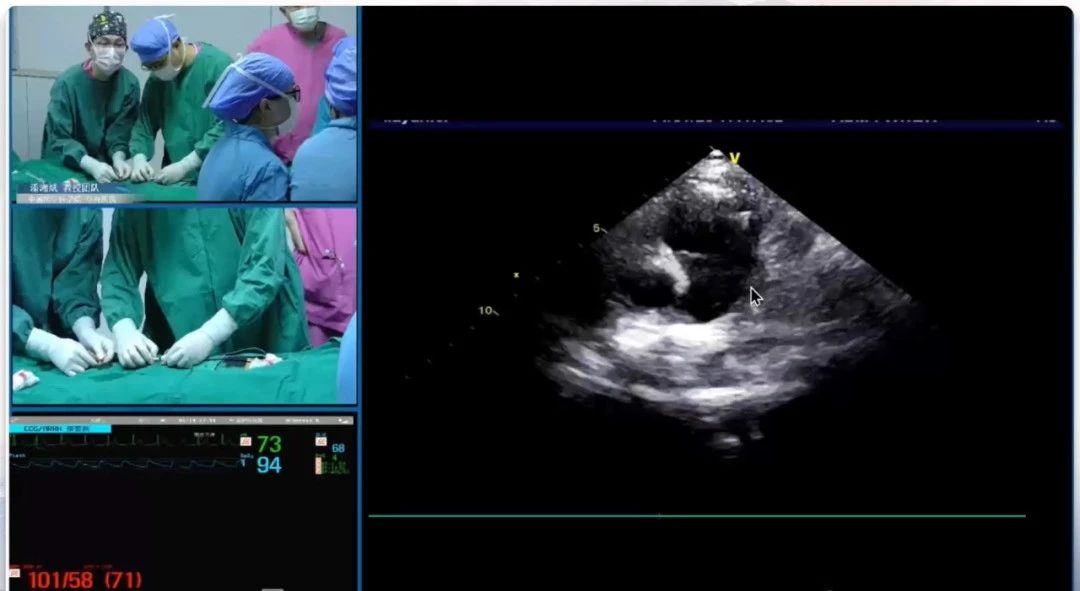

患者为10岁儿童,术前超声评估示降主动脉峡部与左肺动脉间可探及导管,肺动脉侧内径3.5 mm,从长期健康的角度出发,选择采用ABFDQ-II 09(腰高5mm、腰部直径9 mm)全降解封堵器配合9F输送鞘进行封堵。术中采用经股动脉法,在超声引导下,先将导丝+导管送至PDA开口处,导丝通过PDA后退出,调整导管朝向肺动脉,重新送入导丝通过PDA进入肺动脉。于胸骨左缘第3肋间肺动脉长轴切面确认导丝位置合适后,保留导丝,退出导管,送入输送鞘管至主肺动脉。后沿鞘管送入封堵器,先释放肺动脉侧伞盘,回撤整体系统,使封堵器左盘面贴合PDA肺动脉端,继而释放右盘面。经多切面确认封堵器形态良好、骑跨于肺动脉与主动脉间,遂牵拉成型线锁定封堵器。锁定后胸骨旁主动脉短轴切面示封堵器稳固贴合无残余分流,且牵拉试验封堵器整体稳定,盘面无形变,判断已成功锁定。后剪断成型线并撤出钢缆及鞘管,释放后多切面确认封堵器形态良好,无残余分流,封堵成功。

锁定前牵拉测试、锁定后牵拉测试

术后超声